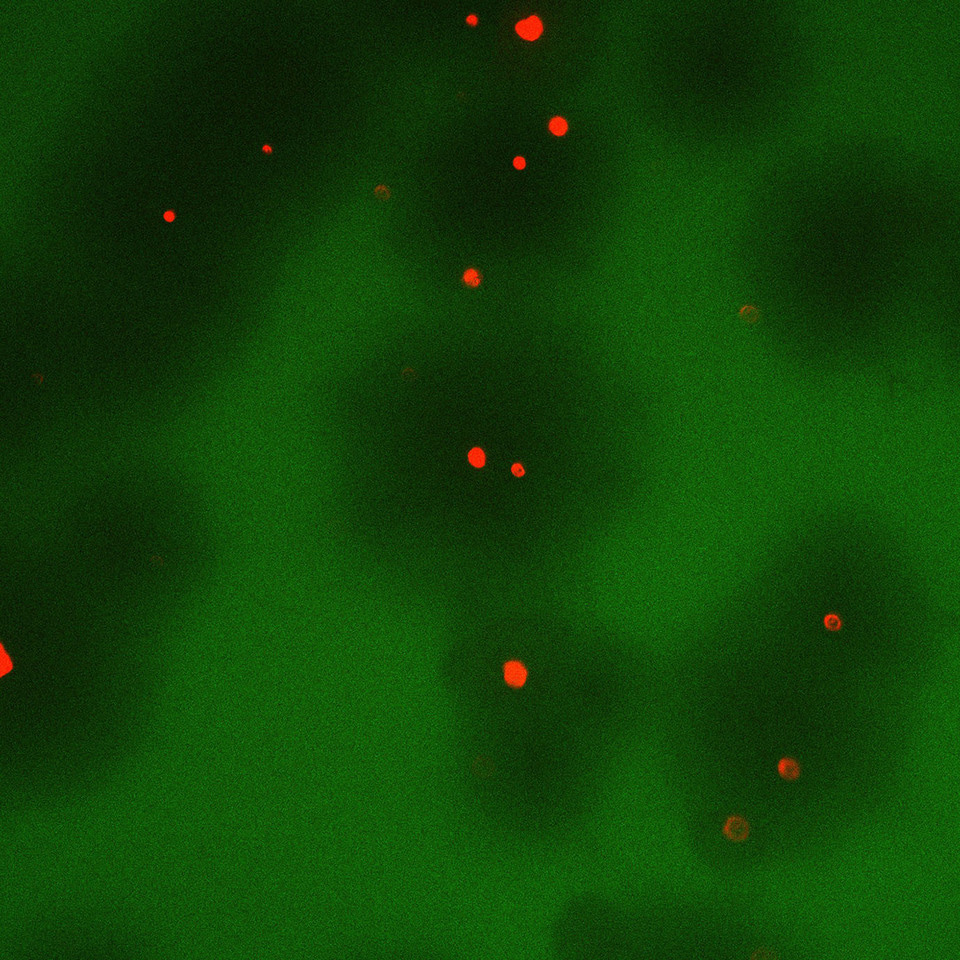

Figure 1: Overall concept of phage therapy for bacterial lung infection. Reproduced from our paper2. SpringerNature.

Our paper just published in Nature Biomedical Engineering2 reports on a project developed to help address this problem. Our work focusses on using bacteriophage (also known as phage; viruses that infect and lyse bacteria) to treat Pseudomonas aeruginosa lung infections. Pseudomonas aeruginosa is the main causative agent of morbidity and mortality in lung infections3,4. Phage are effective against antibiotic-resistant bacteria and are not expected to perturb the commensal microorganisms owing to their narrow range of specificity towards bacteria hosts. Thanks to our collaboration with Dr. Rodney M. Donlan at the Centers for Disease Control and Prevention (CDC), Atlanta, USA, we had a library of several P. aeruginosa phage to choose from and, importantly, excellent expertise to discuss any phage related technical challenges during this project. To facilitate clinical translation and patient compliance, we wanted to target the phage using a dry powder via inhalation. Although phage have previously been shown to be effective against lung infections, their clinical translation through dry powder inhalation route is limited due to a lack of suitable carriers. Their size (50-100 nm) is too small for lung deposition and hence are exhaled out if administered via dry powder inhalation. Hence, in this project, we used our biomaterial-based drug delivery background to synthesize polymeric carriers that can load and deliver phage throughout the lungs. We engineered the size, density and porosity of polymeric particles such that they reach deep lungs after administration through dry powder inhalation5. Such particles also prevent clearance by immune cells due to their large size and form a depot from which phage can release and infect the surrounding bacteria.